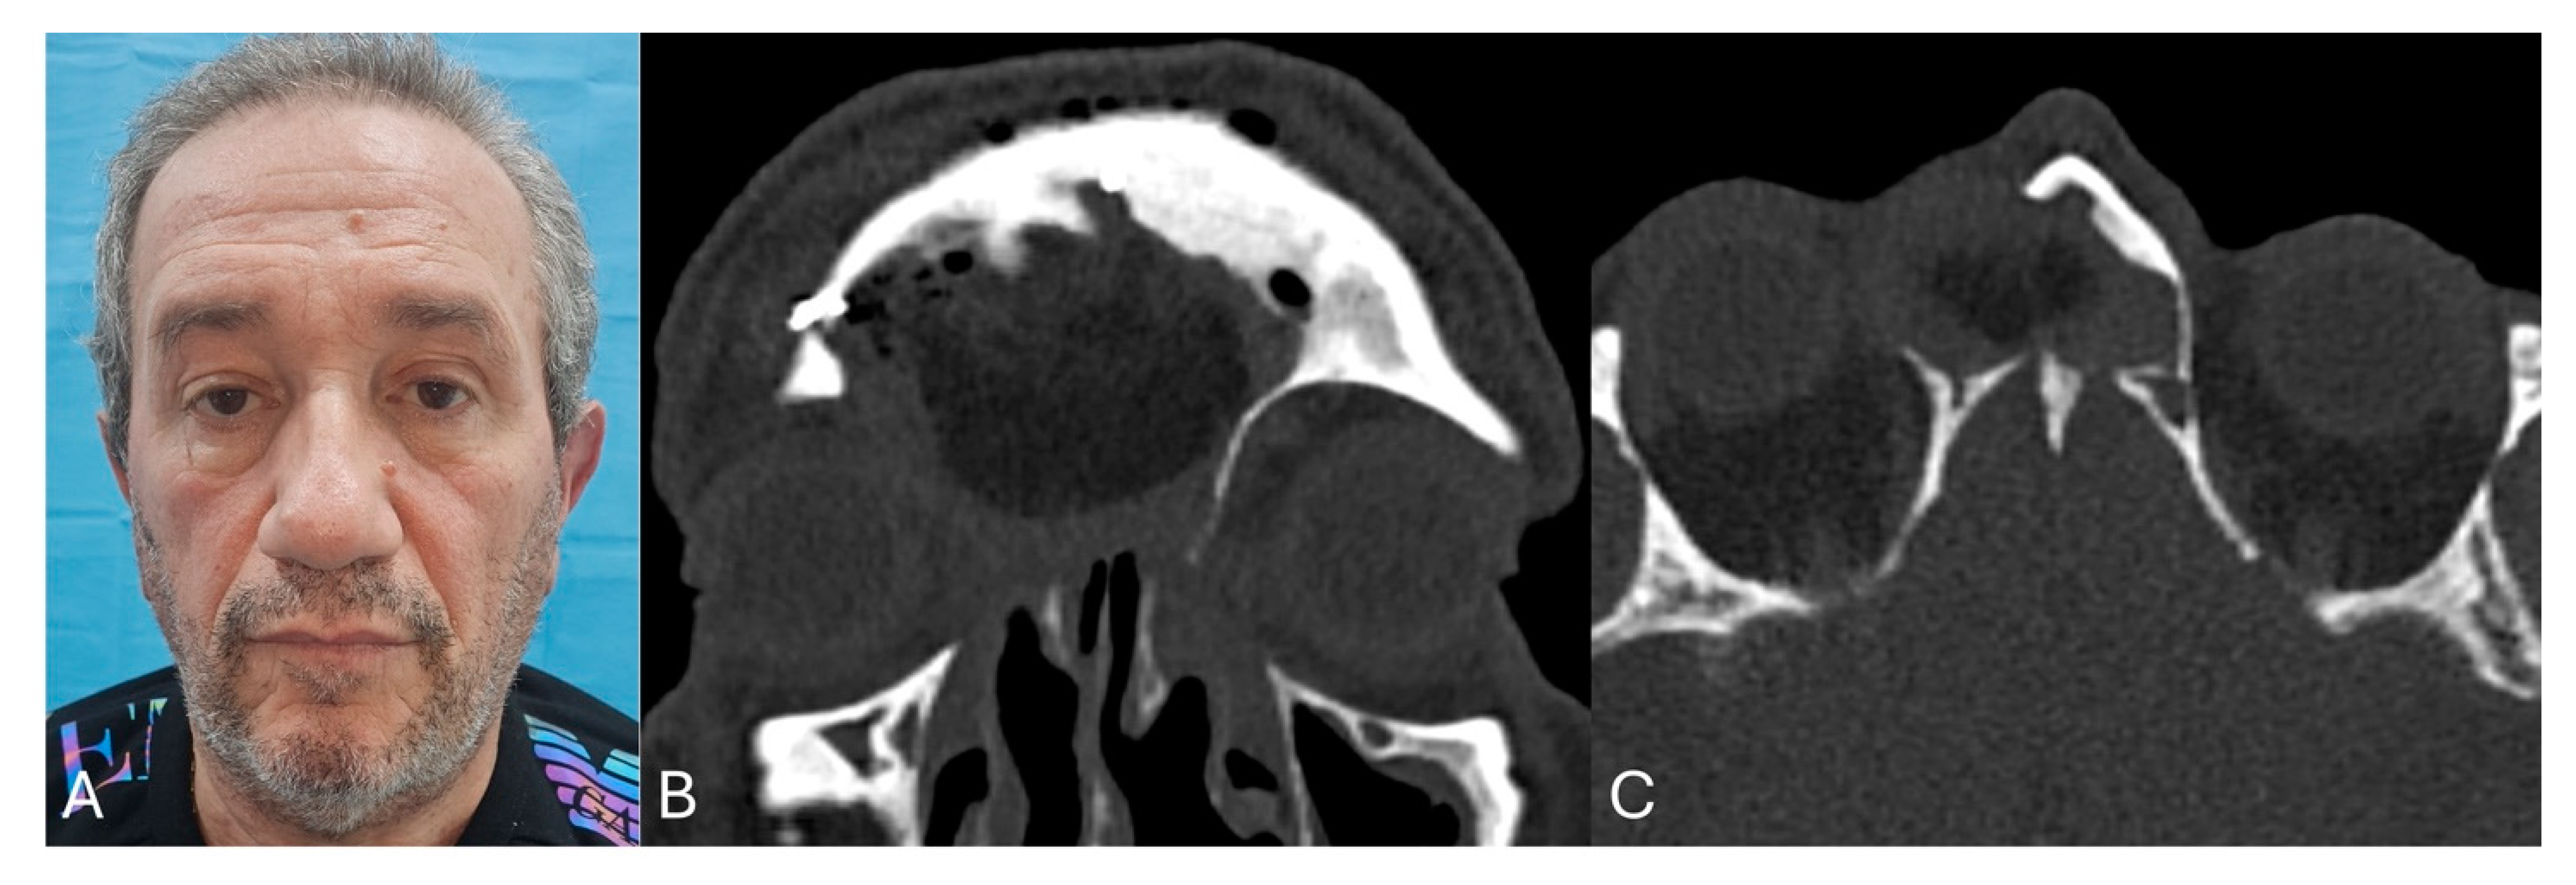

| 1 | M | 47 | Frontal-ethmoidal mucocele | Frontal wall erosion with skin fistulization | 28 min (about 5 h) | 50 months | No | Resolution of the symptom |

| 2 | M | 68 | Recurrent frontal sinusitis | Headache, Rhinorrhea | 26 min (about 5.5 h) | 46 months | No | Resolution of the symptom |

| 3 | M | 53 | Frontal-ethmoidal mucocele | Headache, pain | 25 min (about 4 h) | 43 months | No | Resolution of the symptom |

| 4 | M | 31 | Frontal-orbital-ethmoidal osteoma | Lateral globe dislocation | 23 min (about 5.5 h) | 38 months | No | Partial resolution of the symptom |

| 5 | F | 72 | Recurrent frontal sinusitis | Pain, rhinorrhea, and hyposmia | 22 min (about 5 h) | 36 months | No | Partial resolution of the symptom (hyposmia) |

| 6 | M | 43 | Frontal-ethmoidal mucocele | Headache, pain | 25 min (about 4.5 h) | 30 months | No | Resolution of the symptom |

| 7 | F | 57 | Frontal-orbital-ethmoidal osteoma | Exophthalmos, dystopia, and lateral globe dislocation | 20 min (about 5 h) | 28 months | No | Partial resolution of the symptom |

| 8 | M | 67 | Frontal-ethmoidal mucocele | Headache, pain, rhinorrhea, and frontal wall erosion with skin fistulization | 25 min (about 4.5 h) | 26 months | Recurrence after one year | Headache, pain, and rhinorrea |

| 9 | M | 71 | Recurrent frontal sinusitis | Headache, pain, and rhinorrhea | 23 min (about 4 h) | 24 months | No | Resolution of the symptom |

| 10 | M | 48 | Frontal-ethmoidal osteoma | Asymptomatic | 20 min (about 5 h) | 21 months | No | / |

| 11 | F | 58 | Recurrent frontal sinusitis | Headache, pain, and rhinorrhea, | 21 min (about 4 h) | 20 months | No | Resolution of the symptom |

| 12 | M | 63 | Frontal-ethmoidal mucocele | Frontal wall erosion with skin fistulization | 22 min (about 4 h) | 18 months | No | Resolution of the symptom |